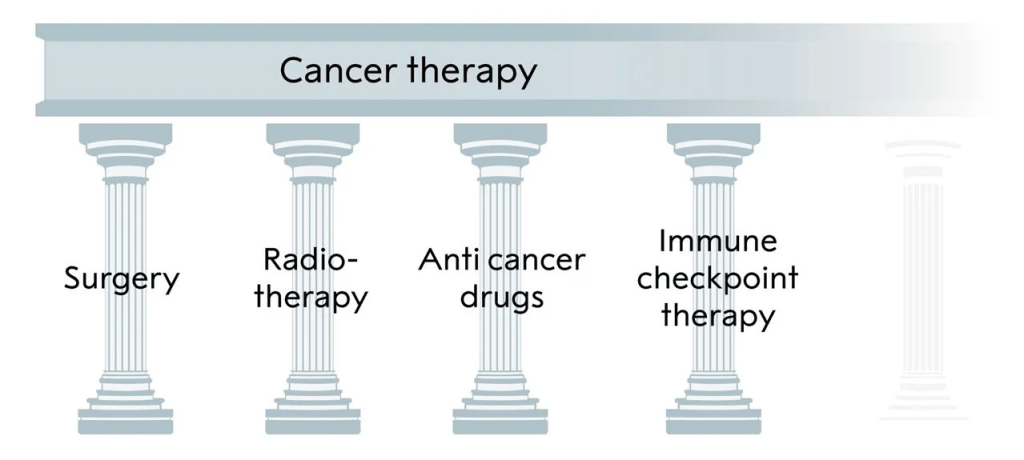

Immense progress has been made in mechanistic understanding of tumor-intrinsic factors that drive cancer progression; however, therapeutic targeting of these factors is often associated with therapy resistance and cancer recurrence. On the contrary, therapies that target tumor-extrinsic factors, such as immunotherapy, generate robust and durable responses in patients across various types of cancer and have emerged as the fourth pillar of cancer treatment. However, current immunotherapies are ineffective in approximately 50% of tumors, particularly immune-cold tumors. This underscores either the inefficacy of existing immunotherapeutic strategies or a lack of understanding regarding tumor-extrinsic factors in these types of tumors, or both. Addressing these knowledge gaps, I believe, can significantly enhance patient survival and reduce cancer mortality, and that is the grounding mission of my research program.

The three pillars of cancer treatment, all directed against the cancer cell, and the fourth, immune checkpoint inhibitor, based on unleashing an immune response against the tumor.